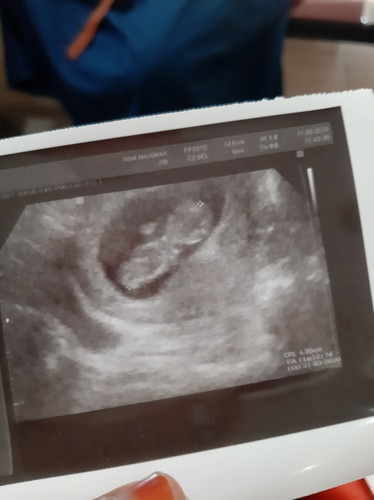

Bu alhamdulillah janinnya sudah keliatan dan kata dokter usianya 11 minggu, saran dong bun makanan yang bagus untuk perkembangan tumbuh sih janin, terima kasih.